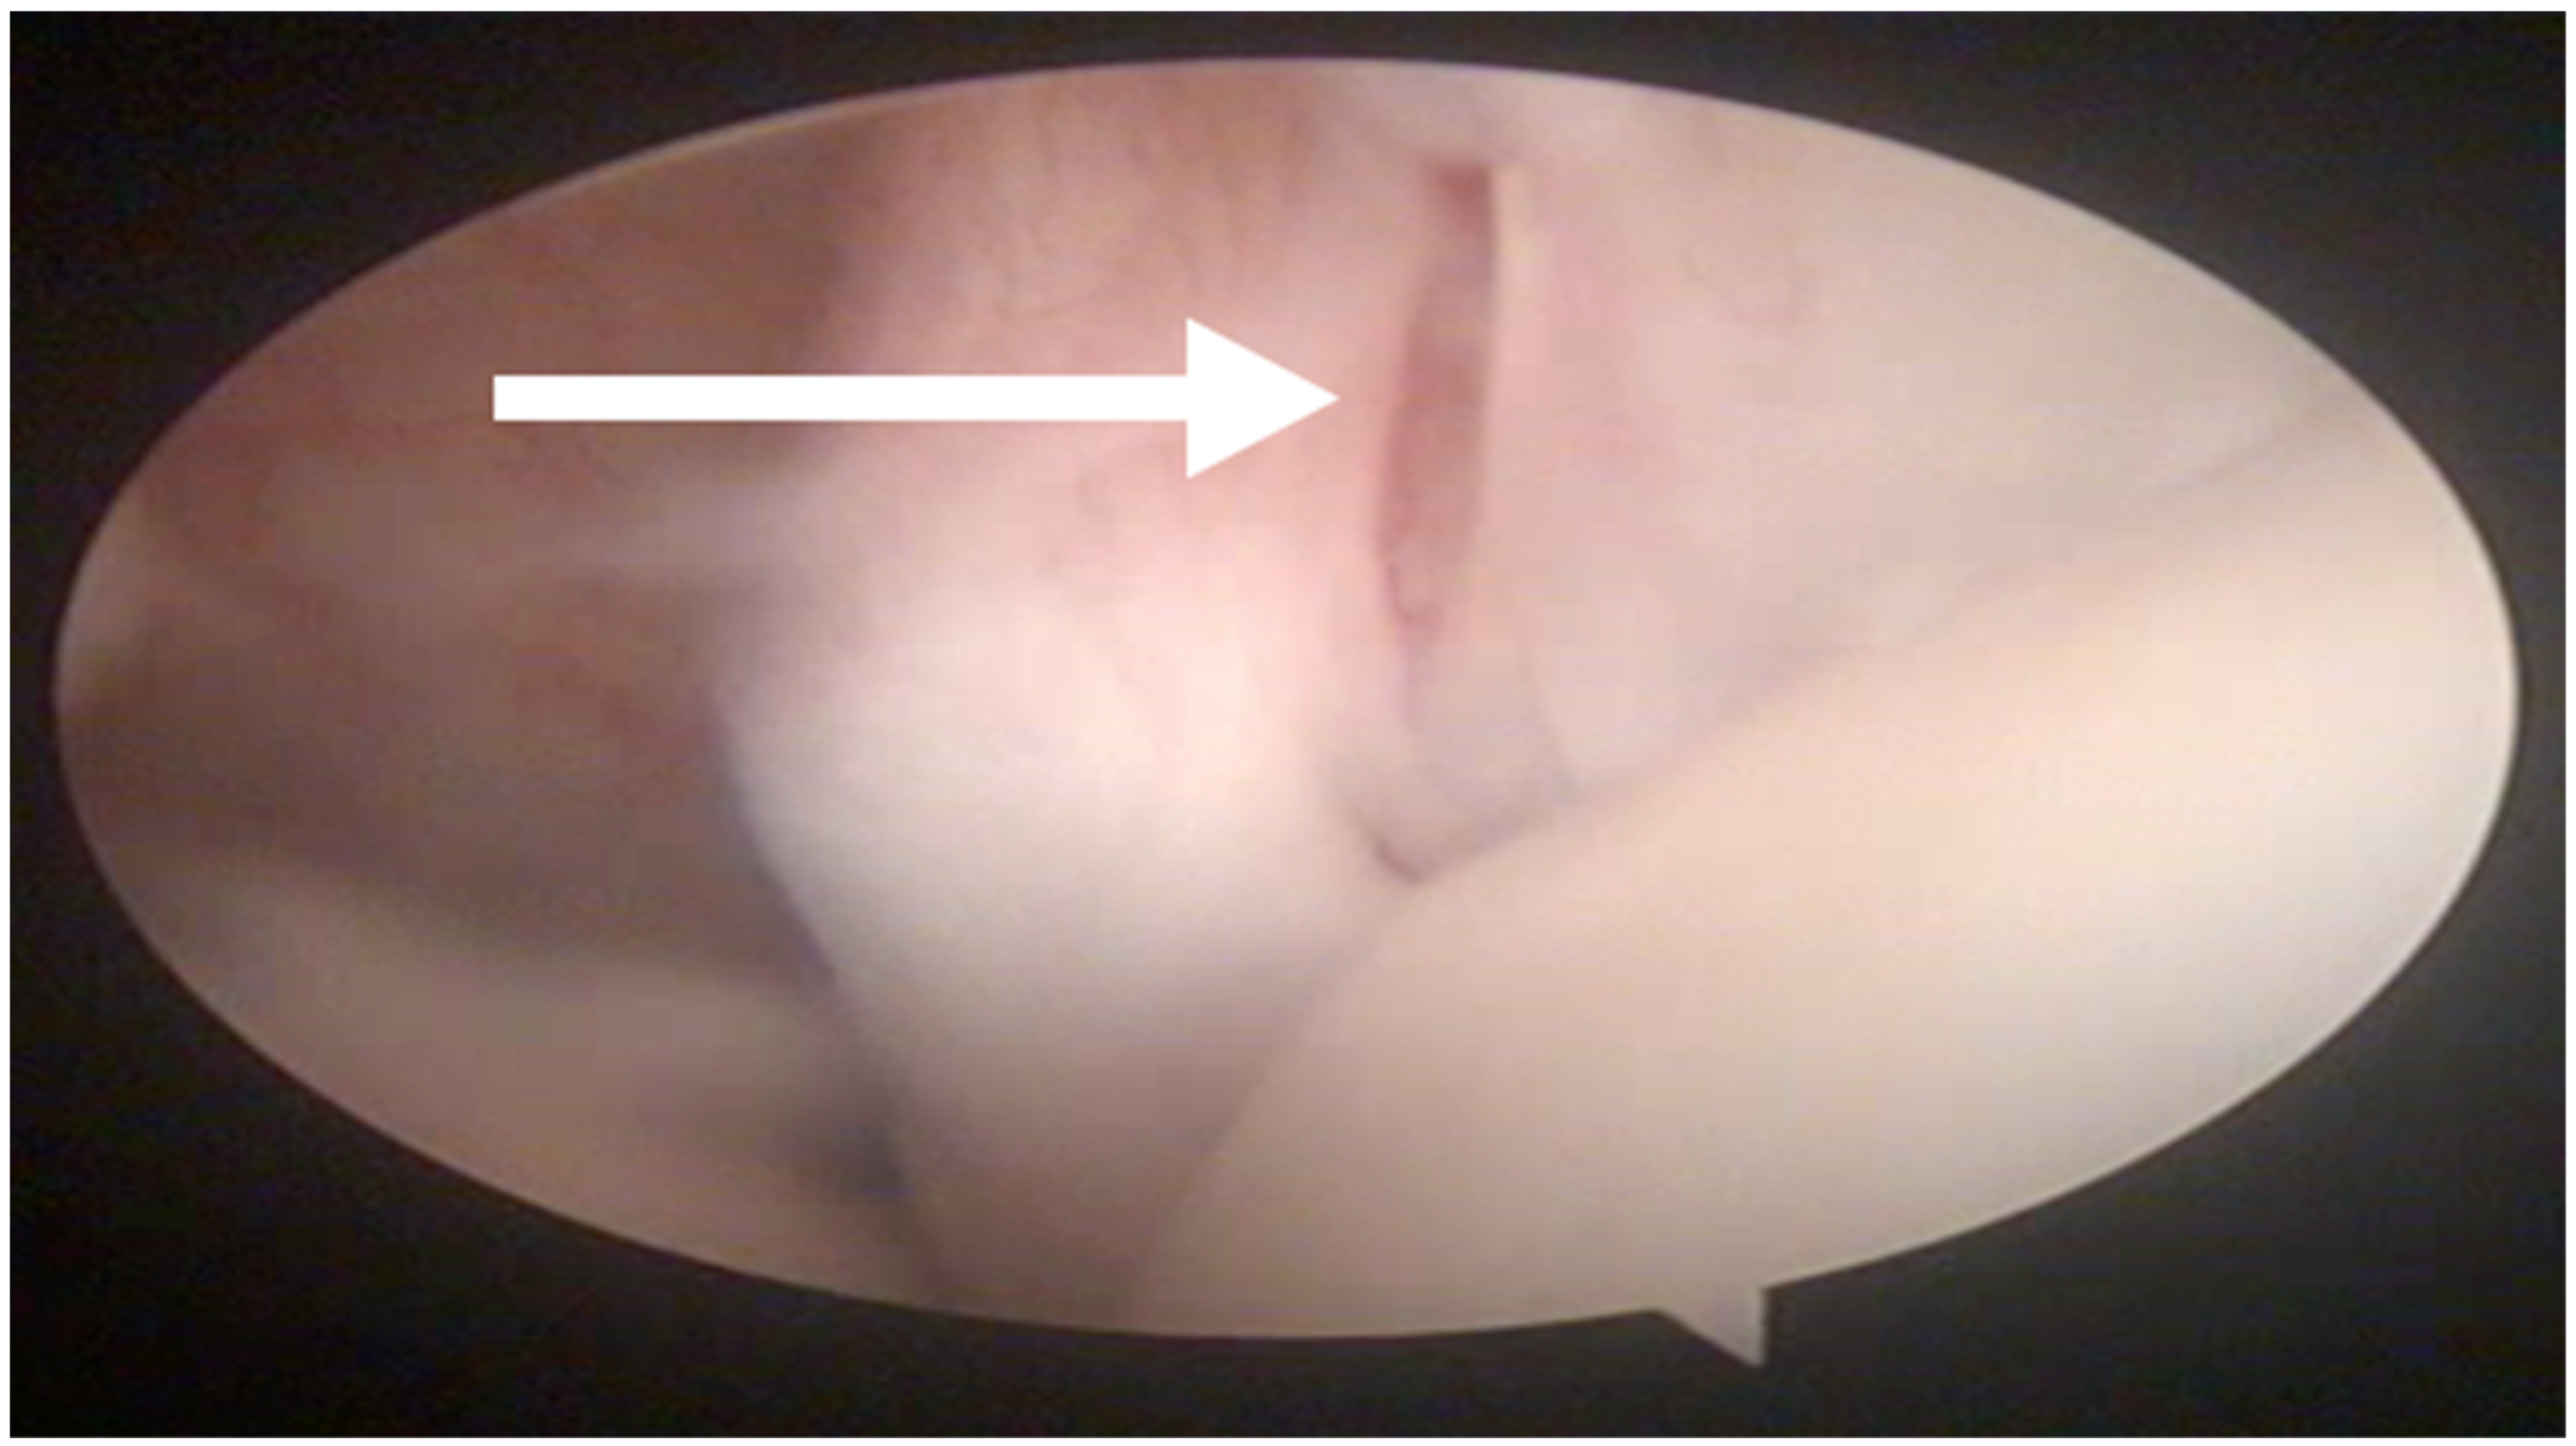

In all the dogs, surgery was performed by the same surgeon only in the shoulder affected by lameness. Intra-articular abnormalities were arthroscopically observed in 13 out of 27 shoulders and consisted of fibrillation of the medial glenohumeral ligament in 3 out of 27 cases, partial rupture of the tendon of the subscapularis muscle in 7 out of 27 cases and laxity of the tendon of the subscapularis muscle in 3 out of 27 cases (Figure 2).

The arthroscopic and MRI findings were in agreement about the absence of intra-articular shoulders abnormalities in 10 out of 27 shoulders. In 13 out of 27 shoulders, the ectasia of biceps brachii tendon was detected with MRI but was not recognized with arthroscopy. In 9 out of 27 shoulders, lesions of the subscapularis tendon, not previously established with MRI, were diagnosed by arthroscopy. In 3 out of 27 shoulders, laxity of the medial glenohumeral ligament, not previously diagnosed with MRI, was observed by arthroscopy. In 27 out of 27 shoulders, both MRI and arthroscopy were in agreement about the lateral glenohumeral ligament integrity. No intra-operative complications were reported. No dogs required physical rehabilitation in the post-operative period.

Figure 2. Arthroscopic evaluation of the tendon of the sub-scapularis muscle. A partial rupture is indicated by the white arrow.